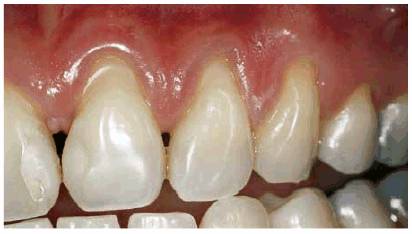

A 28-year-old woman had a severe bulimic condition over the course of many

years (Figures 17-16A 17-16B, and 17-16C). However, she underwent successful

treatment and desired to restore her smile. Since so much tooth structure had

been eroded, it was necessary to place provisional restorations followed by

crown lengthening (Figure 17-16D) and eventual replacement with the

final ceramic-metal restorations (Figures 17-16E 17-16F, and 17-16G

Figure 17-16A: This 28-year-old woman had a history of bulimia. After several years of therapy, she wanted to correct the damage caused by the bulimic condition. Note the severe occlusal erosion.

Figure 17-16B: The labial erosion seen here also contributed to the discoloration that bothered the patient.

Figure 17-16C: This before picture shows the severe labial erosion present on the posterior teeth.

Figure 17-16D: Crown lengthening and build-ups with composite resin were necessary before making the impressions for the final restorations.

Figure 17-16E: The final splinted restorations were constructed using ceramic-metal.

Figure 17-16F: The five splinted crowns restored this attractive lady's smile. Note how light a shade the patient selected.

Figure 17-16G: The new, improved shapes and shade helped to accomplish the smile desired by the patient.